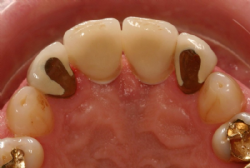

Provisorische Versorgung

Nach der Freilegung der Implantate wurde einer Abformung durchgeführt (Impregum® der Firma Espe®) und ein Meistermodell mit Implanat-Analoga angefertigt.

Zunächst wurden darauf provisorische Kunststoff-Kronen auf Titan-Abutments der Firma Astra Tech® hergestellt. Diese wurden beim Patienten eingegliedert und die Weichgewebs-Situation (Papille, Gingivalrand) über eine Zeitraum von knapp zwei Monaten beobachtet.

Abbildung 4: Provisorische Kronen in situ. Die Öffnung für die Schraube wurde mit provisorischen Kunststoff verschlossen